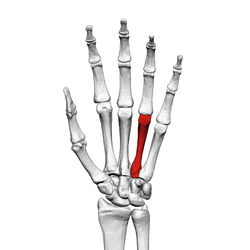

Fourth metacarpal bone

The fourth metacarpal bone (metacarpal bone of the ring finger) is shorter and smaller than the third.

The base is small and quadrilateral; its superior surface presents two facets, a large one medially for articulation with the hamate, and a small one laterally for the capitate.

On the radial side are two oval facets, for articulation with the third metacarpal; and on the ulnar side a single concave facet, for the fifth metacarpal.